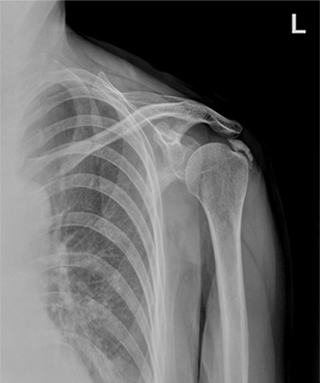

체외충격파 치료 전